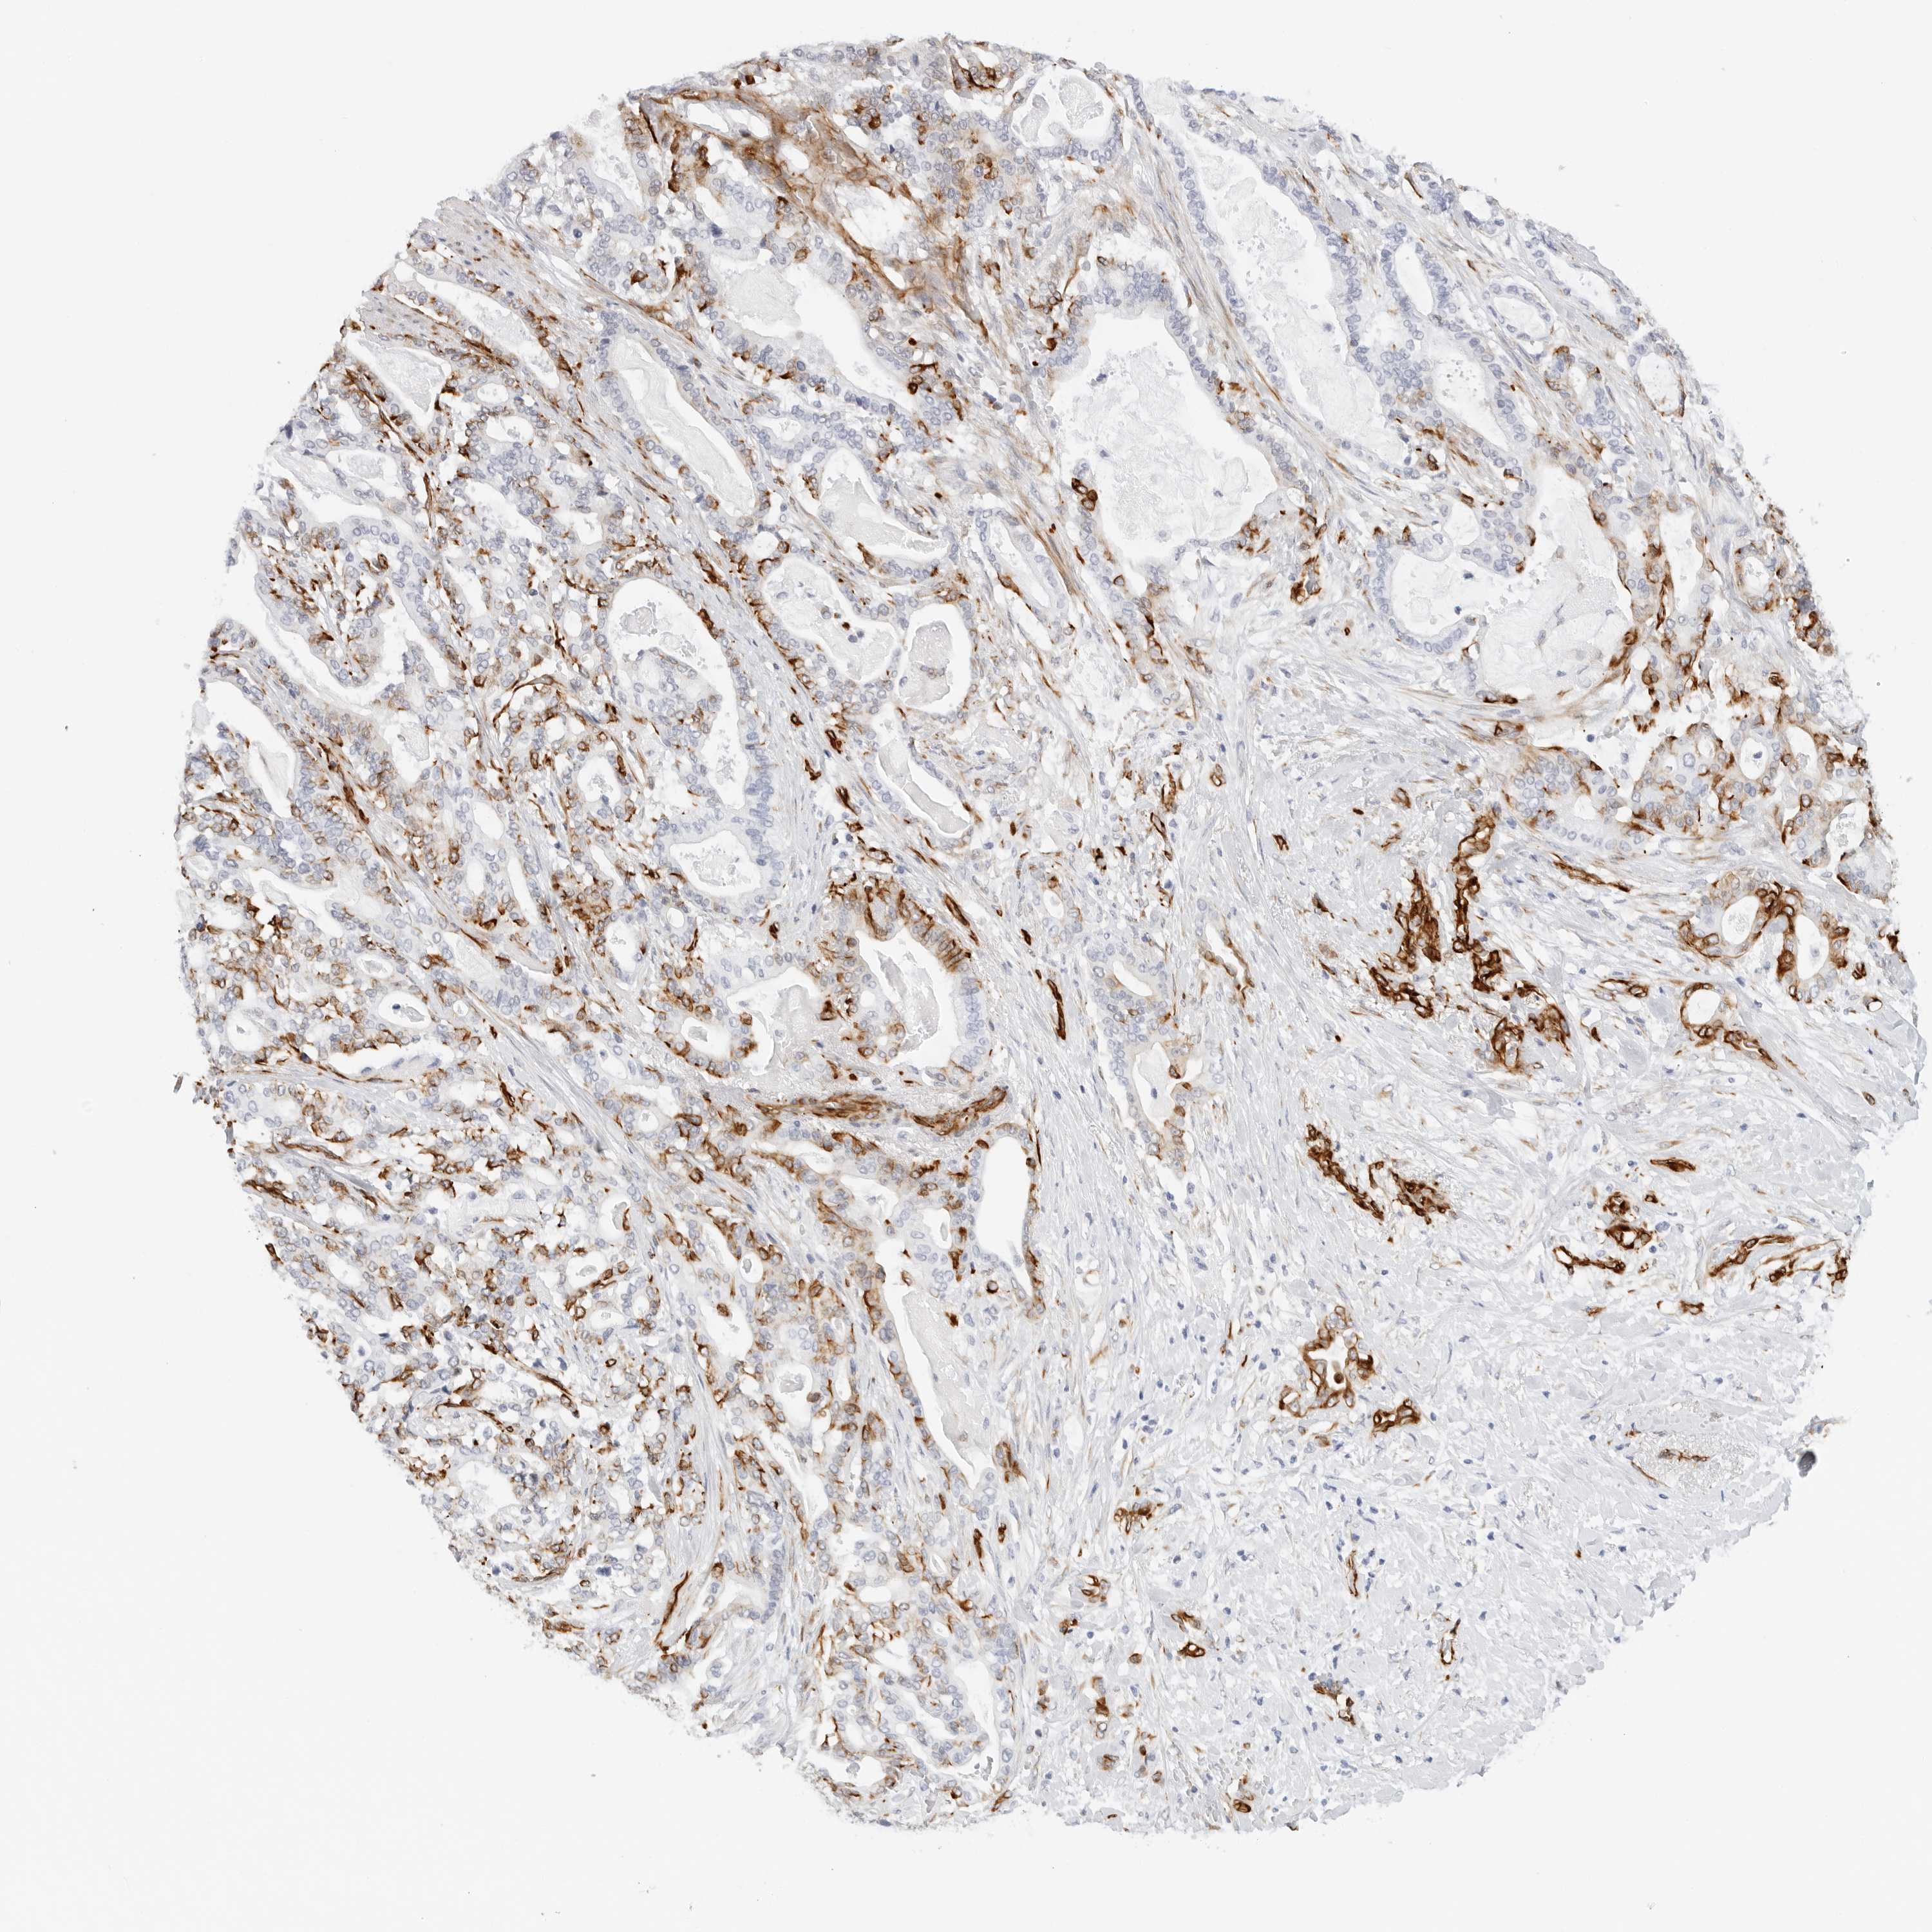

PANCREATIC CANCER - Protein expressioni

A mouse-over function shows sample information and annotation data. Click on an image to view it in a full screen mode. Samples can be filtered based on level of antibody staining by selecting one or several of the following categories: high, medium, low and not detected. The assay and annotation is described here.

Note that samples used for immunohistochemistry by the Human Protein Atlas do not correspond to samples in the TCGA dataset.

Antibody stainingi

Antibody staining in the annotated cell types in the current human tissue is reported as not detected, low, medium, or high, based on conventional immunohistochemistry profiling in selected tissues. This score is based on the combination of the staining intensity and fraction of stained cells.

Each image is clickable and will lead to virtual microscopy that enables deeper exploration of all samples and also displays staining intensity scores, fraction scores and subcellular localization as well as patient and tissue information for each sample.

Antibody HPA007007

Antibody HPA026111

Antibody CAB005889

Antibody CAB058692

Staining

High

Medium

Low

Not detected

Intensity

Strong

Moderate

Weak

Negative

Quantity

>75%

75%-25%

<25%

None

Location

Nuclear

Cytoplasmic/membranous

Cytoplasmic/membranous,nuclear

Adenocarcinoma, NOS

Adenocarcinoma, metastatic, NOS